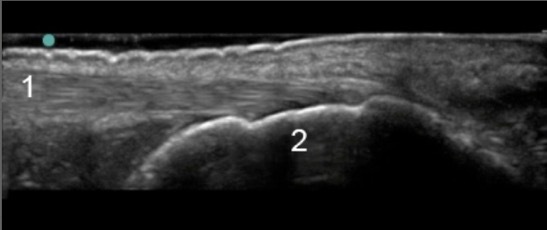

足・足首 アキレス腱踵骨の画像

アキレス腱

踵骨